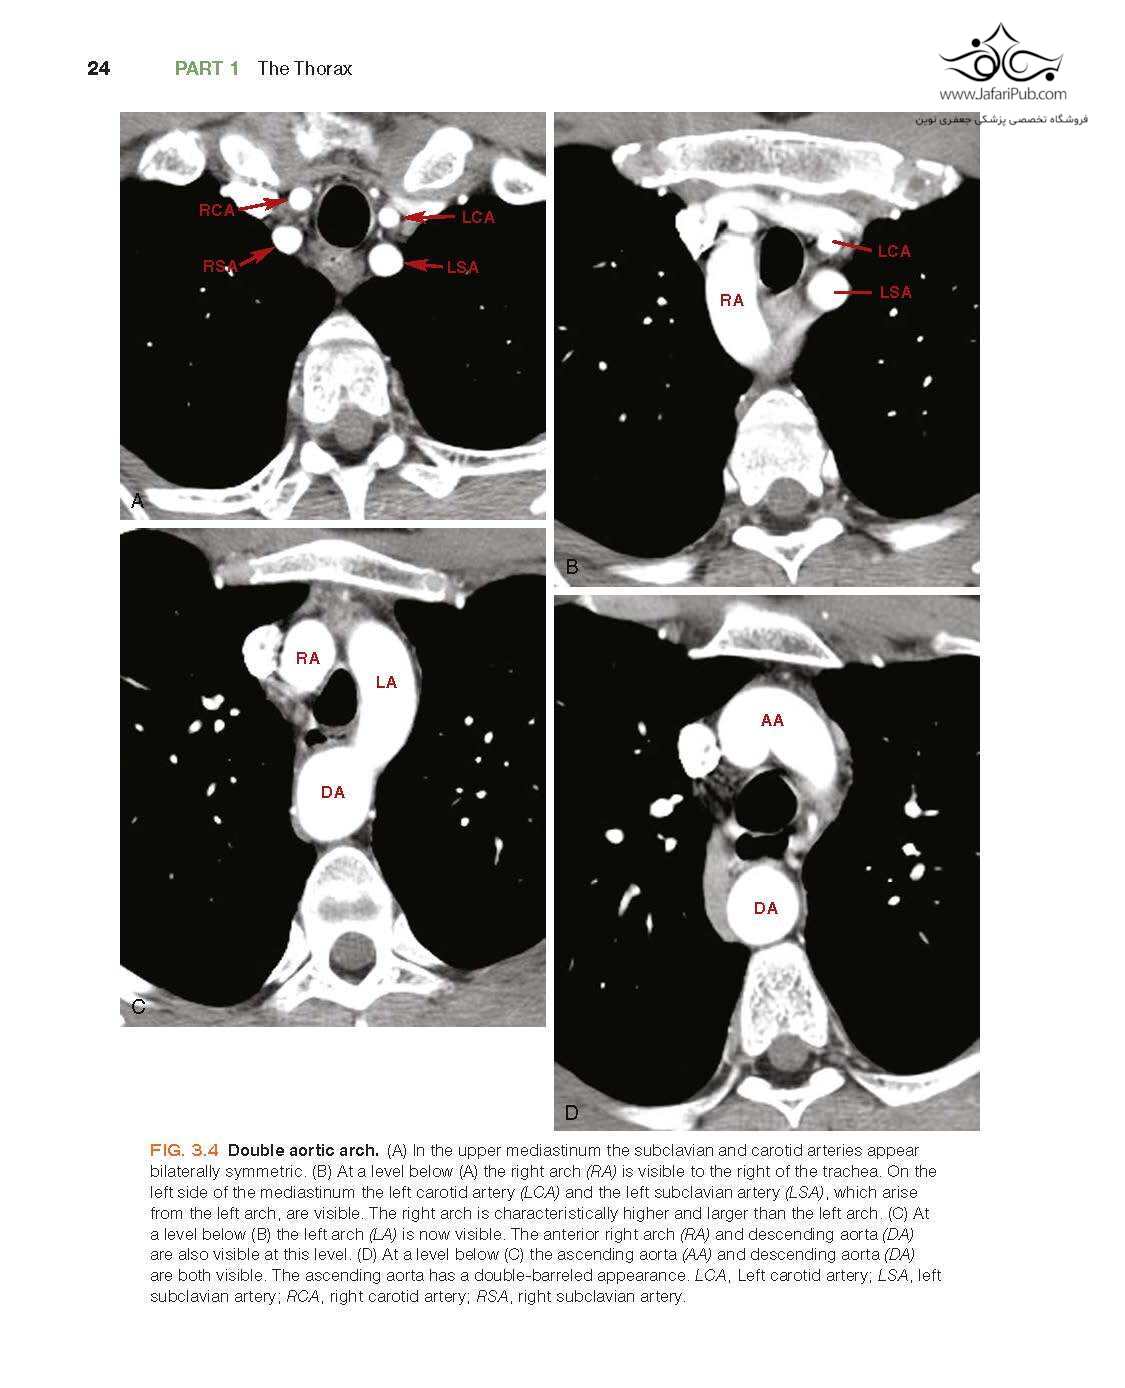

Features many new topics, discussions of additional diseases, and new, high-quality images from cover to cover, including updated descriptions and illustrations of normal anatomy and incidental findings.